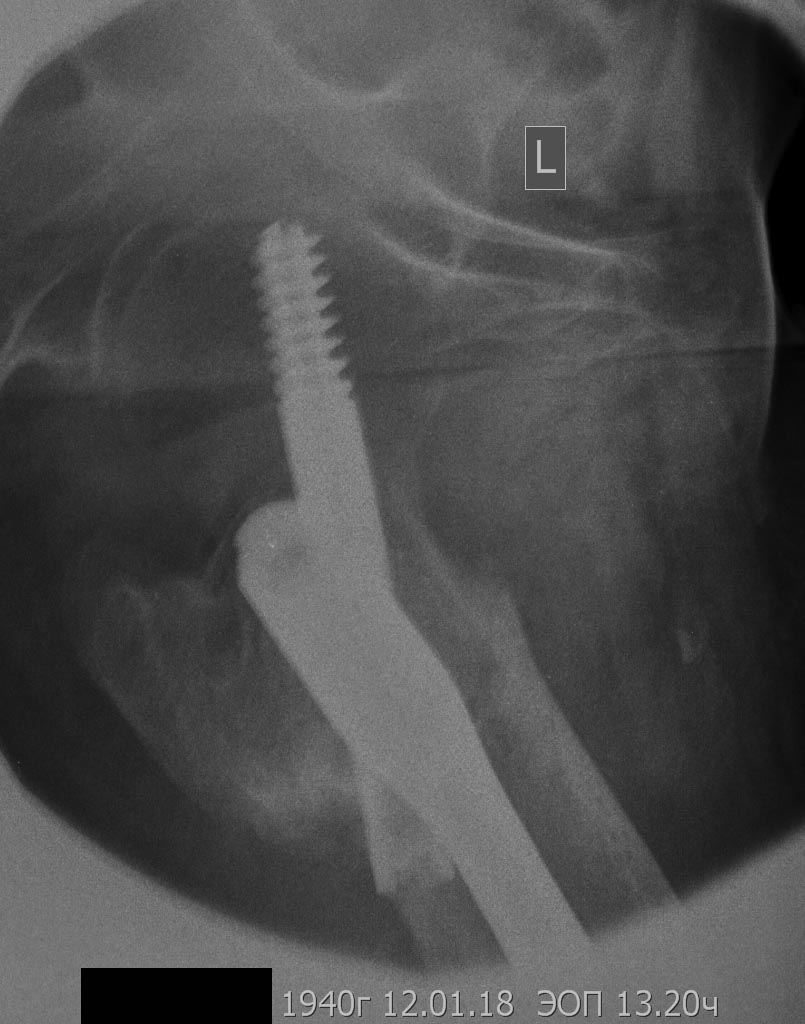

[Ortho] Сросшийся чрезвертельный и перелом н\3 бедра

боковая